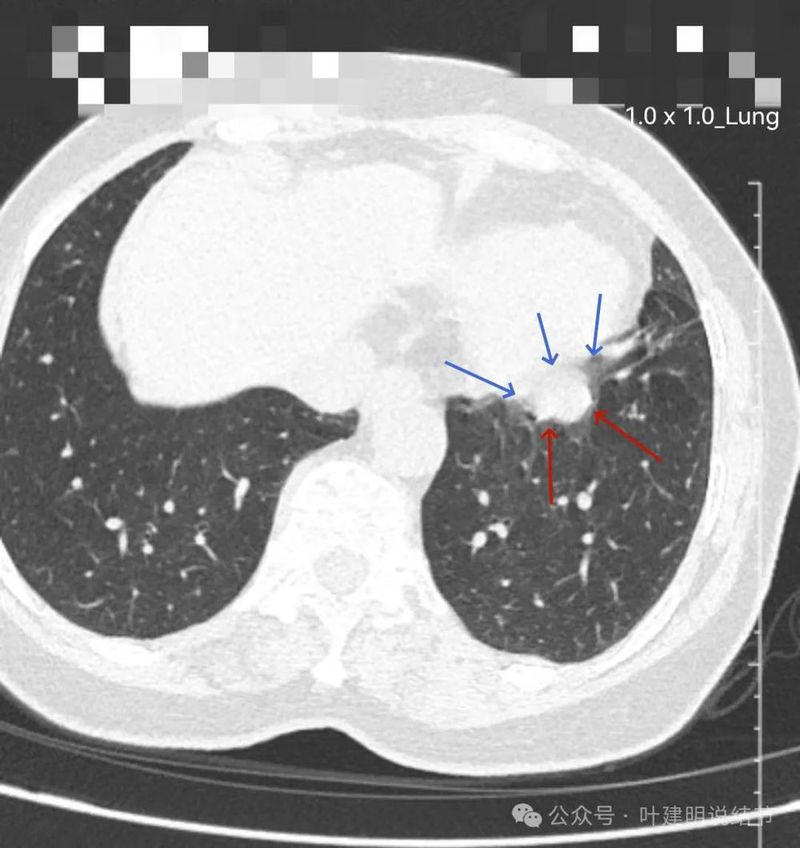

先来看两肺多发病灶的情况:

右上轮廓稍模糊结节,更像少许炎性改变。

胸膜下微小结节,轮廓较清,才1-2毫米,可供分析的影像特征太少,反正先随访。

胸膜下结节两处,也是密度较高,边界较清,但还很小。